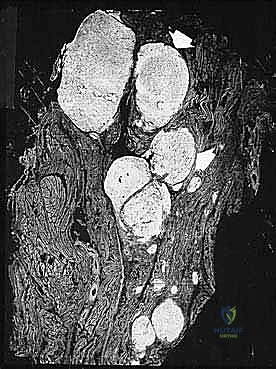

* الساركوما الشحمية (Liposarcoma).

المرحلة الثانية: إعادة البناء العظمي (Skeletal Reconstruction)

بعد إزالة جزء من العظم (أو المفصل بأكمله)، يجب سد الفجوة. تتعدد الخيارات التقنية التي يوفرها الدكتور هطيف في صنعاء:

1. المفاصل الصناعية الكبيرة (Megaprostheses): مفاصل معدنية متطورة (من التيتانيوم) تُصمم خصيصاً لتعويض العظم المفقود، وتسمح للمريض بالحركة المبكرة.

2. الطعوم العظمية (Bone Grafts): استخدام عظم من بنك العظام (Allograft) أو من المريض نفسه (Autograft)، مثل نقل عظمة الشظية مع أوعيتها الدموية لضمان التئامها السريع.